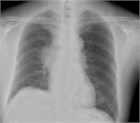

病態

1. 上大動脈症候群とは、上大静脈の閉塞や狭窄によって生じる上半身からの静脈血の還流障害により、静脈圧の上昇を来し、頭部、顔面、上肢、頚部および上半身のうっ血・浮腫を来す症候群である。

1. その原因として肺癌など胸部悪性疾患が多く、腫瘍に関連する救急疾患(Oncologic emergency)の1つに位置づけられている。